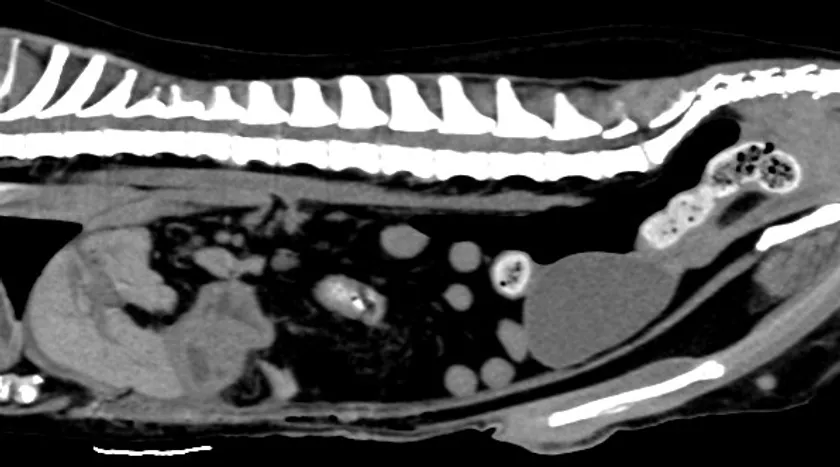

■CT検査

X線を用いて対象を360度方向から連続的に撮影することで全身の断層像を短時間で得ることができます。得られる情報は非常に多く、悪性腫瘍の浸潤範囲や転移検索、臓器の形態的異常などを詳細に評価することができます。

CT検査画像

GE社製 64列128slice CT装置 Revoluion EVO